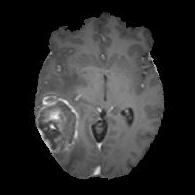

We argue that the sub-optimal paradigm of processing different abstractions within a single CNN pipeline can be remedied through the effective processing of information in a structured manner. Consequently, we devise strategies for disentangling the edge and texture information within a single training pipeline. Figure 2 illustrates how our proposed module, dubbed EG-CNN, can be paired with any existing CNN encoder-decoder to improve segmentation quality near intensity edges. We have applied our EG-CNN to the tasks of brain and liver tumor segmentation in medical images (Figure 3).

(1) Brain MR (2) Liver MR (3) Liver CT (4) Lung CT